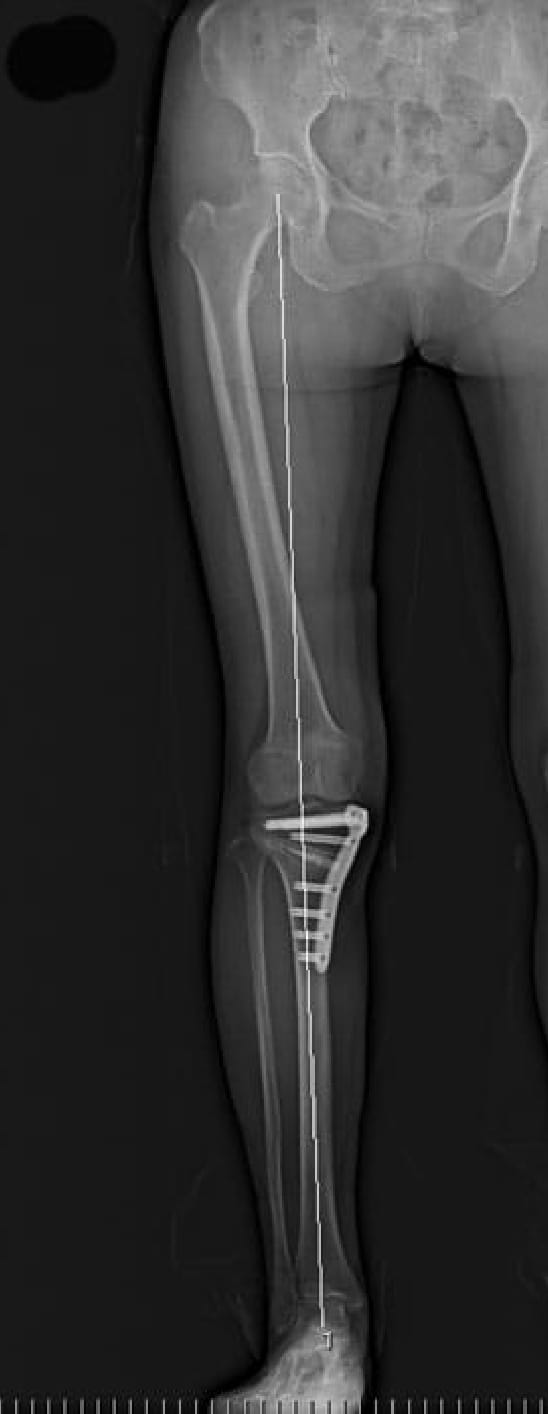

骨入り術は脛骨(すねの骨)の一部分に切れ目をいれて、あいだを広げ、O脚となっている脚を軽度のX脚に矯正した状態で、プレートで固定する手術です。痛みの原因になっている箇所にかかる体重を他の箇所に変えることで、痛みがとれ、また痛んだ軟骨が再生することも知られています。

手術前/O脚

手術後/X脚

プレートと呼ばれる金属の板で骨切りした骨を支えます。骨が癒合するまではプレートが重要な役割を果たします。したがって、骨が癒合したのちに抜去することが可能です。抜去は必須ではないので、各患者さん個人と相談して抜去するかどうかを決定しています。